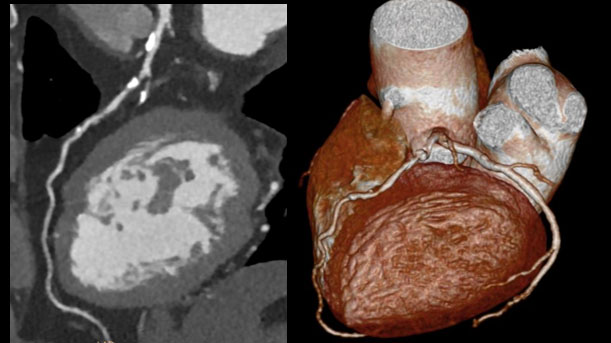

- Precise Cardiac: Zero-click technique designed to improve high heart rate cardiac imaging by compensating for cardiac motion.

- Precise Suite Incisive cardiac